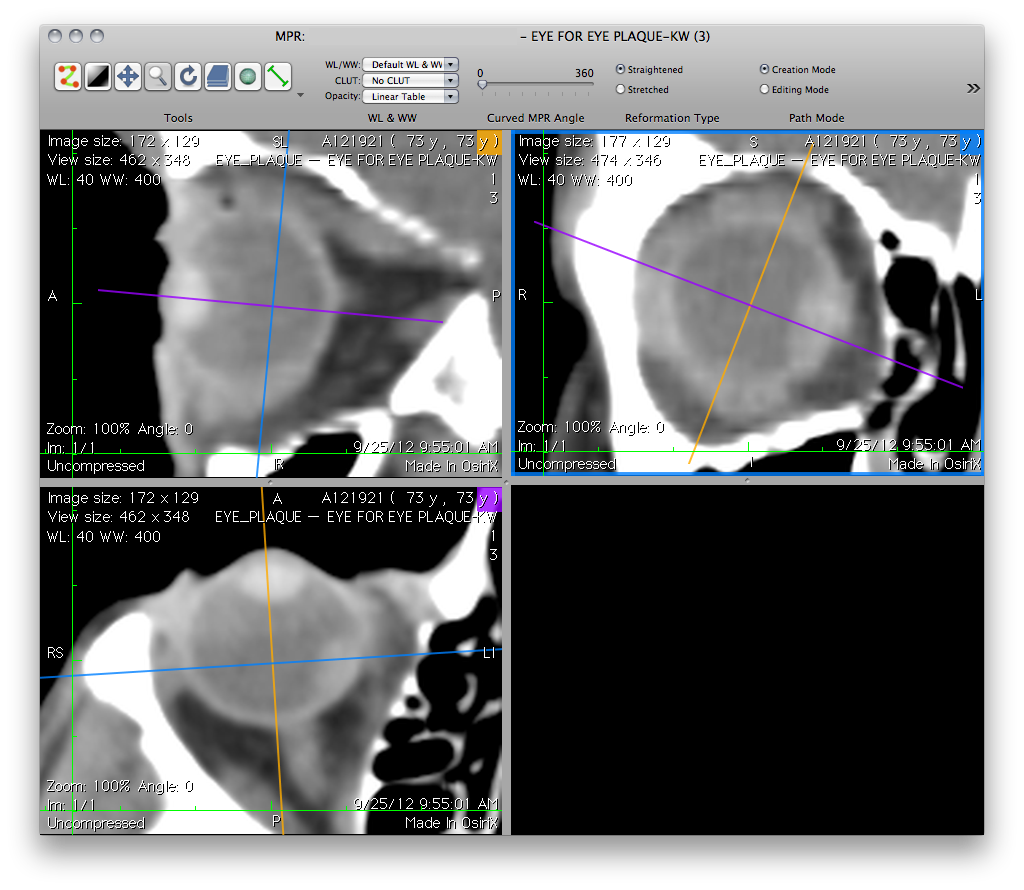

OsiriX: Preparing meridian and coronal reconstructions through the tumor apex for export to Plaque Simulator

• Rotate the crosshairs in the coronal reconstruction pane to create a meridian reconstruction that intersects the tumor apex. The meridian reconstruction will appear in either the the upper left or lower left quadrant depending upon how far you rotate the crosshairs in the coronal pane. In this example it is the lower left quadrant.

• In the meridian reconstruction (e.g. lower left quadrant), translate the blue line away from the equator to create a coronal reconstruction (upper right quadrant) that also intersects the tumor apex.

• Export as .jpg files in the same way as the axial, equatorial and sagittal images. Name the meridian reconstruction 'T-Meridian.jpg'. Name the coronal reconstruction 'T-Coronal.jpg'.

OsirixTumorApexPlanes.png